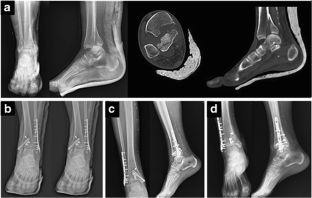

Fig. 2